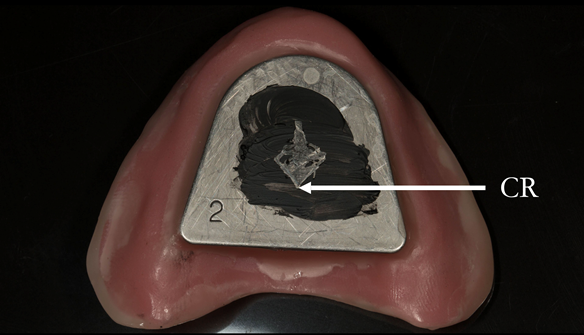

This newsletter describes in step by step detail Anne's transition from an immediate complete upper denture to a definitive complete upper denture.

The clinical situation and treatment process is shown in detail below with photographs. In addition, threre is a link to the a 45 minute webinar I gave explaing this case. I provided the clinical work and Rowan Garstang provided the technical work.